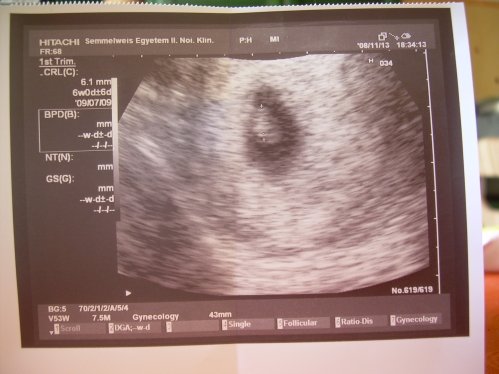

Írjál sokat,hogy vagy,mit érzel...olyan jó nosztalgiázni.Réka név nekem is tetszik.Ez új nekem.Máshol is végzik ingyenesen az anyai vérből a szűrést.Ugye jól gondolom ez a genetikai?Ha jól tudom 80%-ban szuper az eredmény.